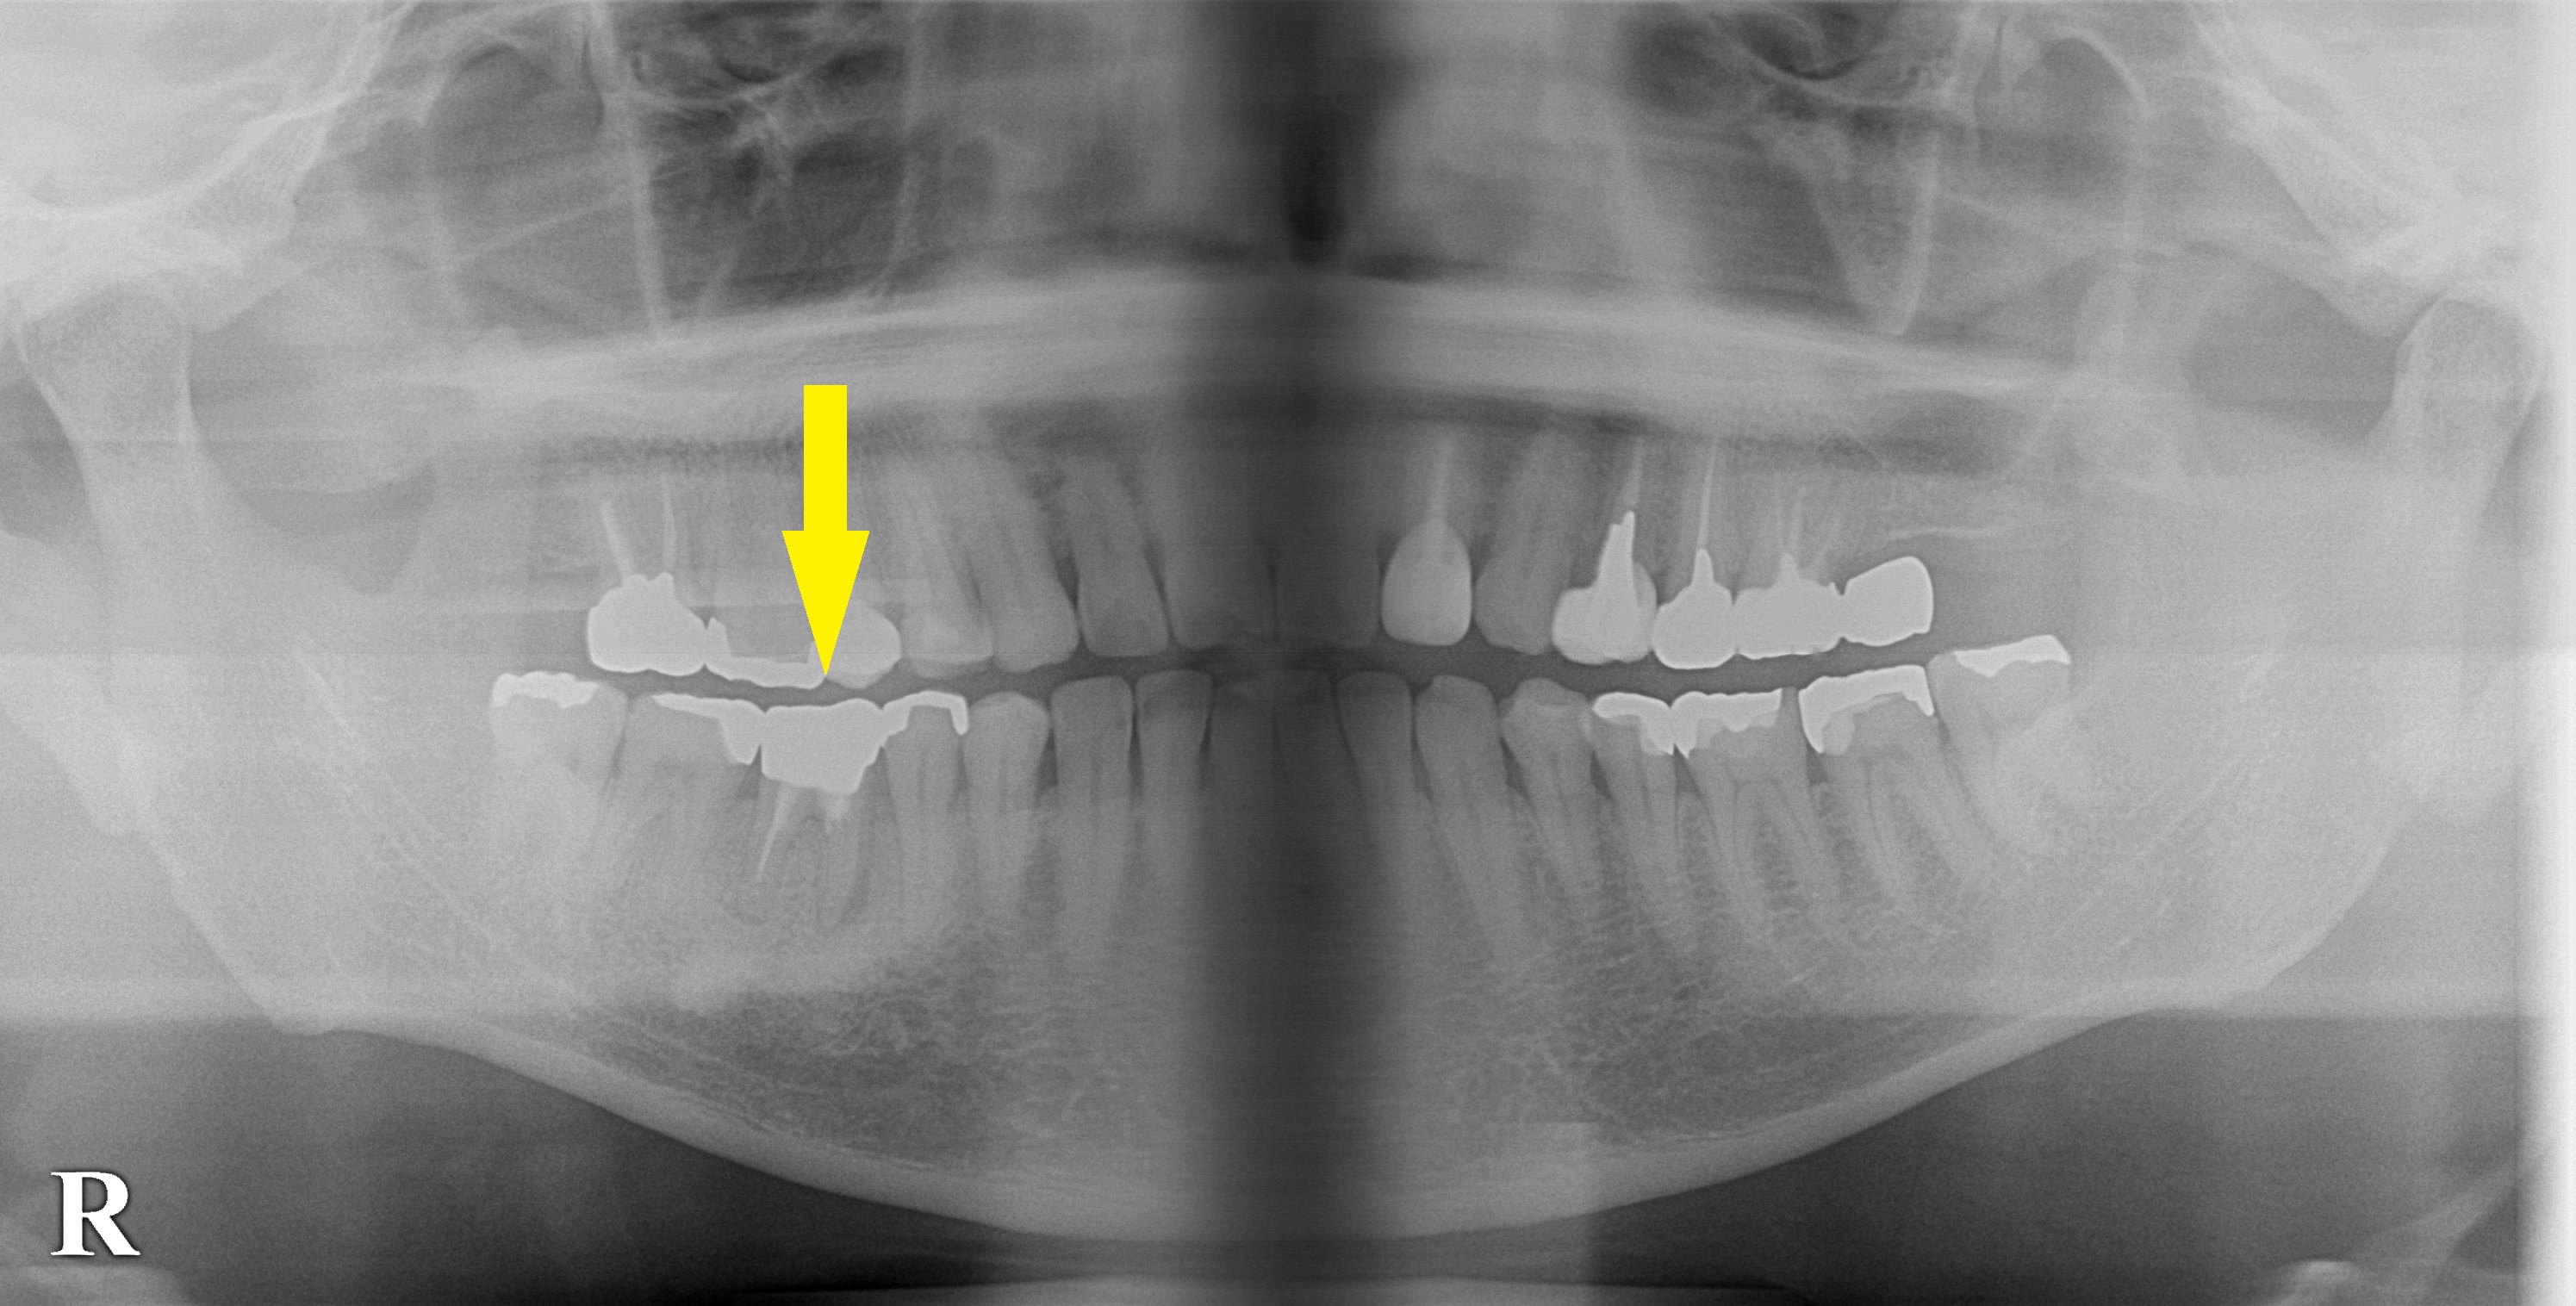

レントゲン写真、CTを撮影してみると、歯根の周囲の骨が吸収されていて、膿がたまっている状態でした。